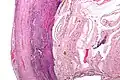

Pathology

Even for clinically certain appendicitis, routine histopathology examination of appendectomy specimens is of value for identifying unsuspected pathologies requiring further postoperative management.[75] No sign of appendicitis in specimens, negative appendectomy, varies but has been estimated to occur in 13% of specimens.[76] Notably, appendix cancer is found incidentally in about 1% of appendectomy specimens.[77][78]

Pathology diagnosis of appendicitis can be made by detecting a neutrophilic infiltrate of the muscularis propria.

Periappendicitis (inflammation of tissues around the appendix) is often found in conjunction with other abdominal pathology.[79]

-

Micrograph of appendicitis and periappendicitis. H&E stain. -

Micrograph of appendicitis showing neutrophils in the muscularis propria. H&E stain. -

Acute suppurative appendicitis with perforation (at right). H&E stain.